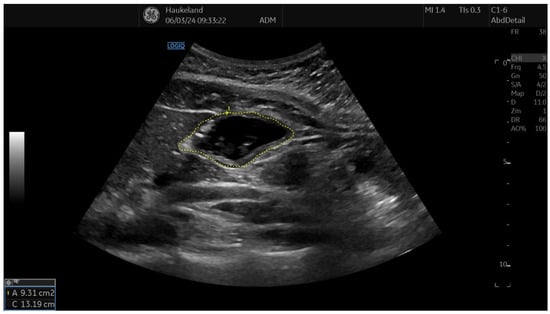

The distal part of the stomach is defined as the antrum region and has been shown to have several disturbed mechanisms in functional dyspepsia patients, such as delayed gastric emptying and antroduodenal dysmotility. To view the antrum adequately, the following approach has been used: the ultrasound probe was placed vertically in the epigastrium to achieve a sagittal plane, with the superior mesenteric vein and aorta serving as internal landmarks [20,22,24,25,26,29]. In this projection, an image of the cross-section of the antrum was achieved [22,25,26,29]. They were different approaches to calculating the cross-sectional antral area, and they differed geographically. Norwegian studies obtained antrum area by tracing around the proper muscle layer of the antral wall (Figure 5) [5,20,27]. Japanese studies traced the antral mucosa [26,29]. Bolondi et al. calculated the cross-sectional antral area by measuring longitudinal and anteroposterior diameters from the outer profile of the antrum wall and applying it in a dedicated formula [25]. Cross-sectional antral area calculations were used to identify both antral distensions, delayed gastric emptying, and antral dysmotility [22].

Figure 5. This image shows the cross-sectional view of the antrum using 2D-US and is used to assess gastric emptying and antrum motility. Cross-sectional view of the antrum was obtained by placing the transducer vertically in the epigastrium to achieve a sagittal plane with the superior mesenteric vein and aorta serving as internal landmarks. Using this image, the cross-sectional antral area was measured by tracing around the proper muscle layer of the antral wall. This image was taken after meat soup ingestion as part of the UMAT at Haukeland University Hospital, Bergen, Norway.